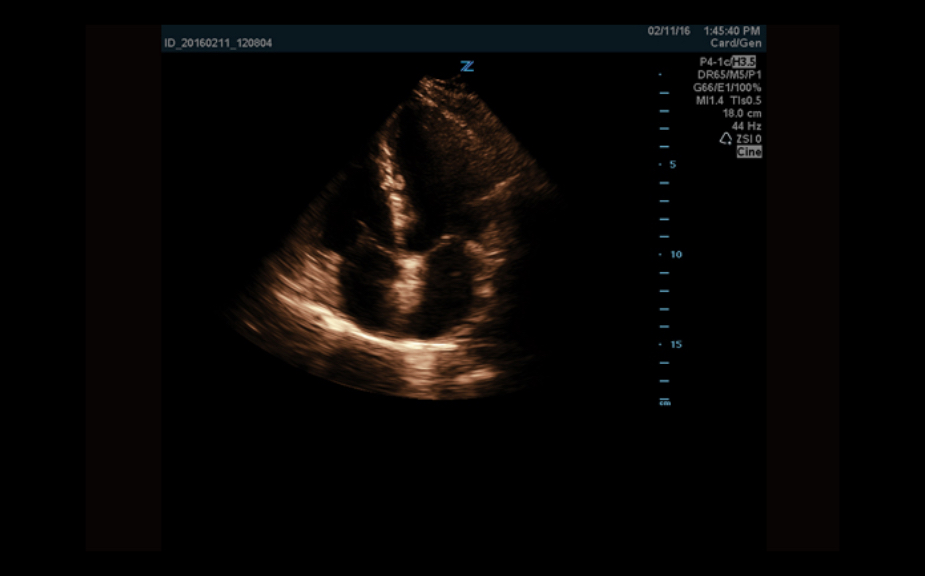

Equipped with patented, software based ZONE Sonography? Technology (ZST), the Z.One PRO provides optimally detailed B-mode and Doppler imaging for patients, regardless of body habitus, helping assure a reliable diagnosis.

Throughout a wide range of applications, the Z.One PRO is the ultrasound solution for your demanding clinical challenges.

- Unsurpassed image quality across all applications

The Z.One PRO ultrasound imaging platform offers a complete family of lightweight transducers that feature both extended broadband capabilities and multi-frequency flexibility delivering exceptional clarity and enhanced detail resolution even at the deepest depths. The C4-1 transducer can penetrate throughout the field of view while maintaining exception spatial and contrast resolution.